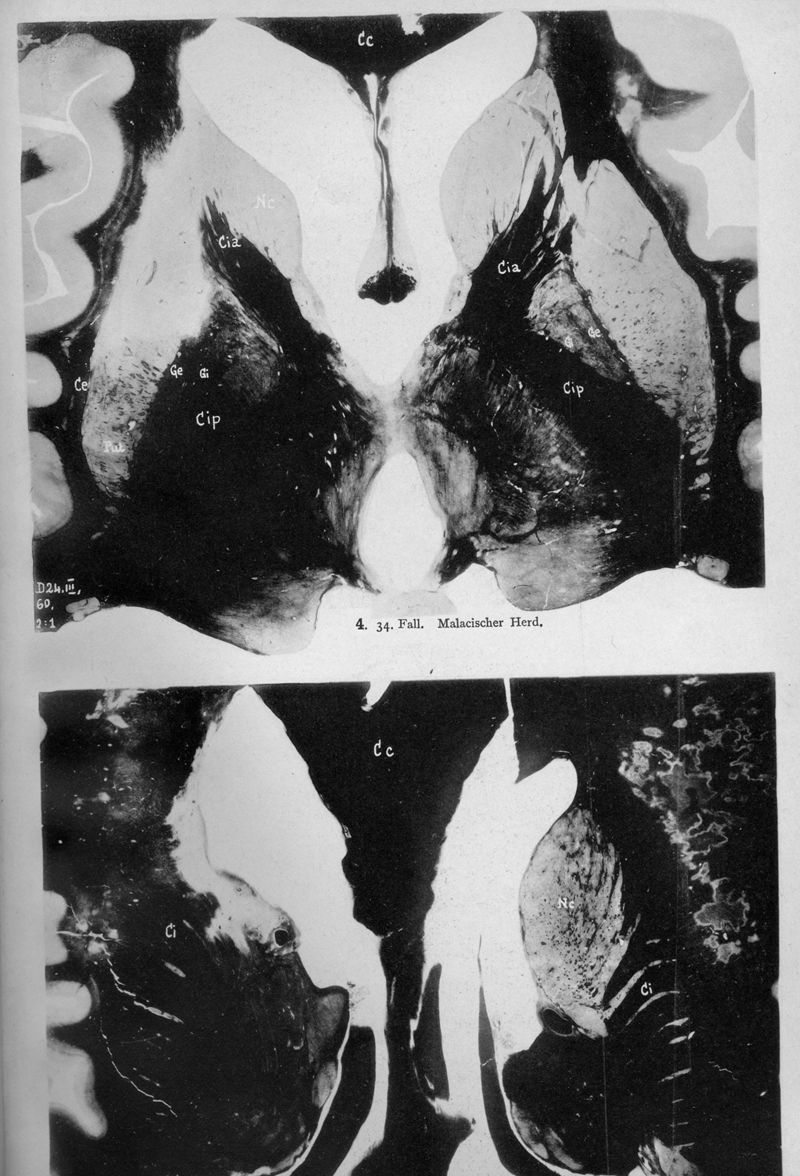

VOGT, Cécile / VOGT, O.

In : Journal für Psychologie und Neurologie,

1920, Vol. 25, pp. 627-846